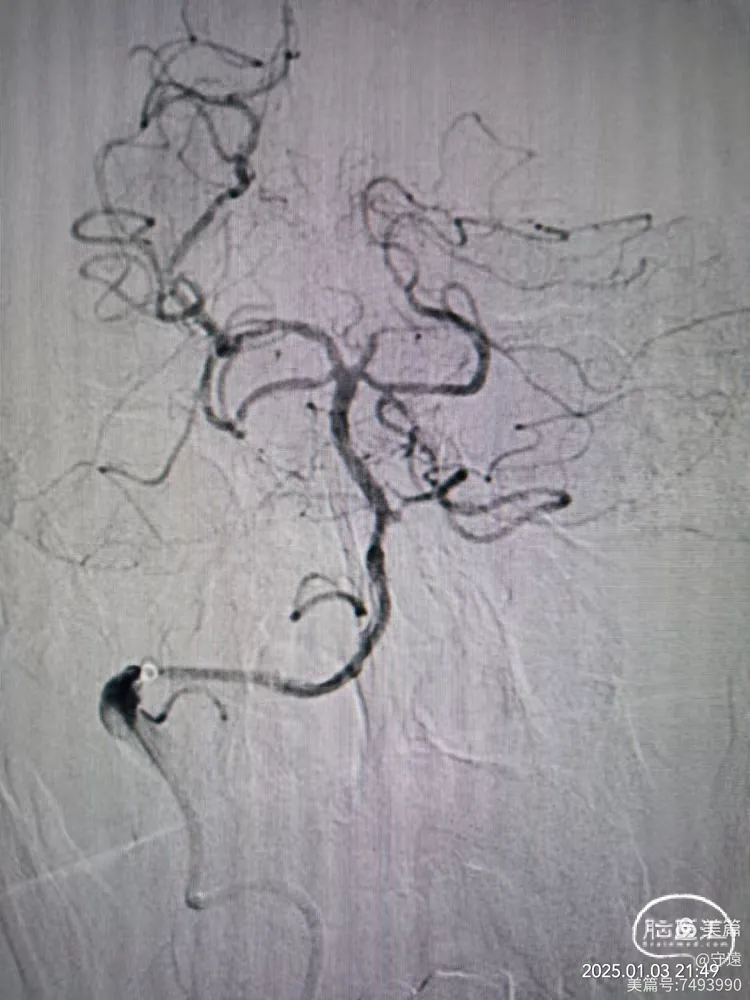

微导管造影显示Ⅴ4狭窄。

微导丝携带2.5*15mm球囊在V4~基底动脉下段扩张。

撤出球囊血管,造影显示再次闭塞,考虑夹层或回弹可能。

球囊穿梭:跟进抽吸导管至狭窄部位,再次输送球囊至狭窄部位。球囊半含状态下再次在7个大气压下扩张。

撤出球囊,踹马桶抽吸出暗红色血栓。

微造影显示:血管再通

回撤导管至V3段造影,狭窄不明显,血流通畅。